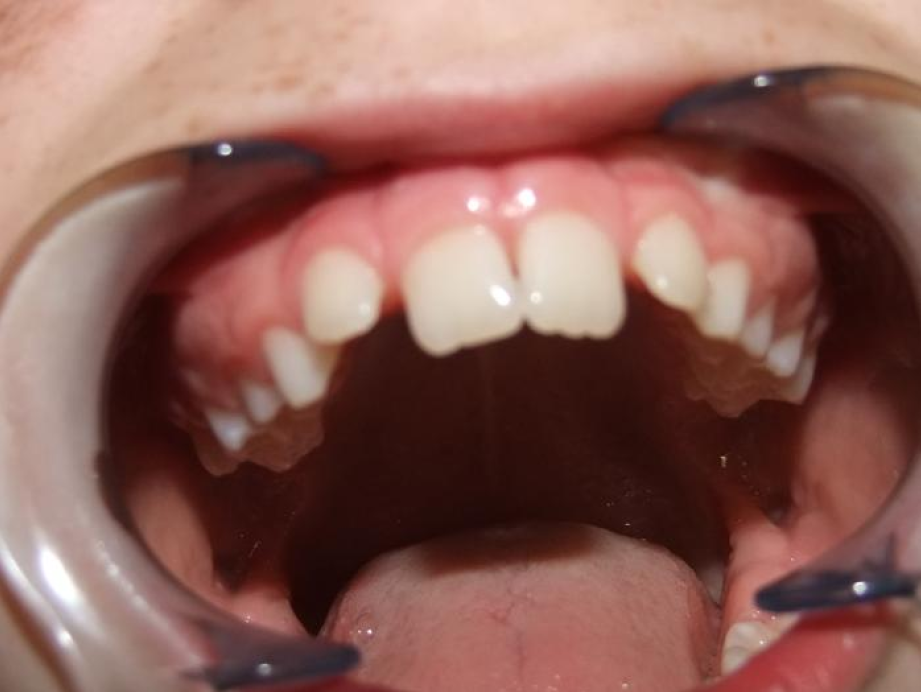

eindfoto

Leeftijd bij aanvang: 9 jaar